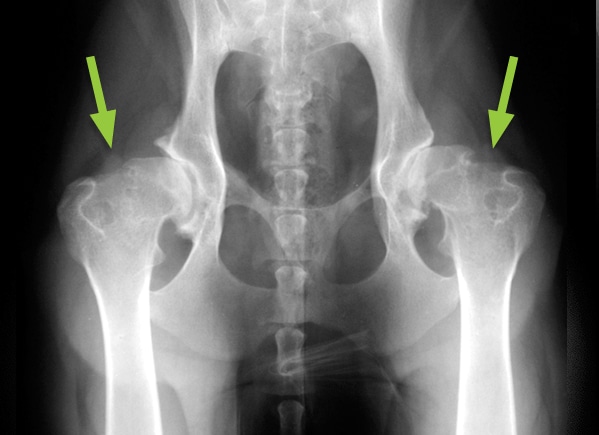

Cranial Cruciate injuries in Dogs

Cranial Cruciate Injuries in Dogs Are related to the knee joint (stifle joint) of the dogs that impart serious walking complications to dogs. The main reason for such injuries is the degeneration of the cruciate ligament supporting the stifle joint. It induces pain and ultimately lameness in dogs. What is the function of the Cruciate […]